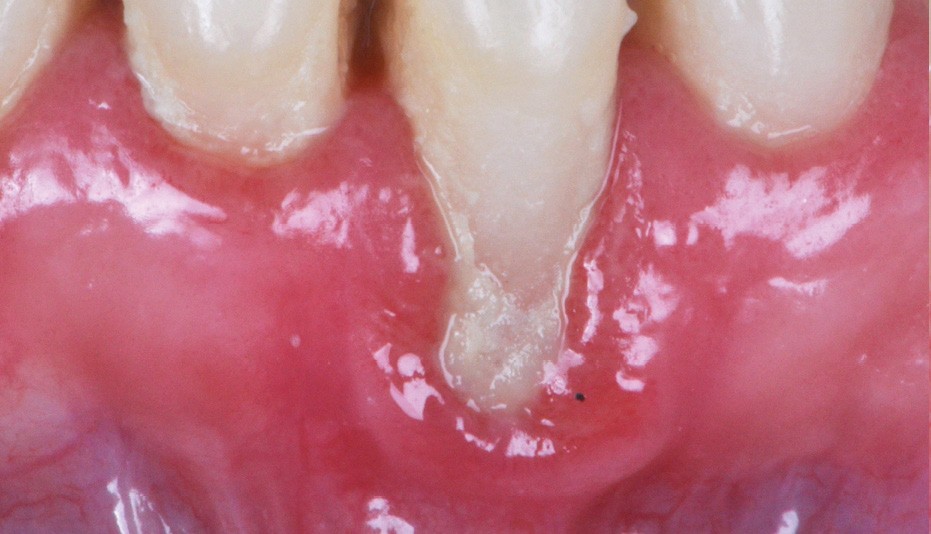

Zuchelli et coll. [1] définissent quatre causes à l’origine des récessions gingivales à la suite d’une déhiscence osseuse : les causes traumatiques (fig. 1) par le brossage, le surcontour prothétique, les piercings ; les causes bactériennes (fig. 2) liées à une inflammation marginale ; les causes virales par le virus de l’herpès simple ; et les origines mixtes, à savoir traumatiques et bactériennes (fig. 3). Le diagnostic de récession liée à la plaque dentaire dépend de la présence de dépôts tartriques et/ou d’inflammation des tissus environnant les zones exposées. En présence d’une origine mixte, la récession est d’abord initiée par un brossage traumatisant, rendant la surface radiculaire hypersensible ou irrégulière, ayant une répercussion négative sur le brossage et l’accessibilité à l’hygiène.